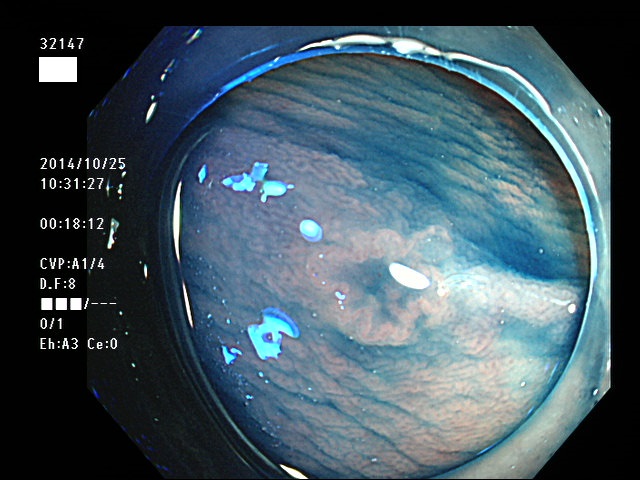

上記100名より抽出した平坦・陥凹型腺腫(=癌化の危険が高いが見落としやすい病変)の内視鏡写真

32101 32103 32105 32107 32108 32109 32110 32113 32114 32115 32116 32118 32119 32121 32123 32126 32129 32131 32132 32133 32134 32135 32138 32140 32141 32142 32143 32146 32147 32149 32150 32151 32152 32153 32154 32155 32156 32159 32160 32161 32163 32164 32167 32168 32173 32175 32176 32178 32183 32185 32187 32189 32190 32191 32194 32195 ・・・・の56名